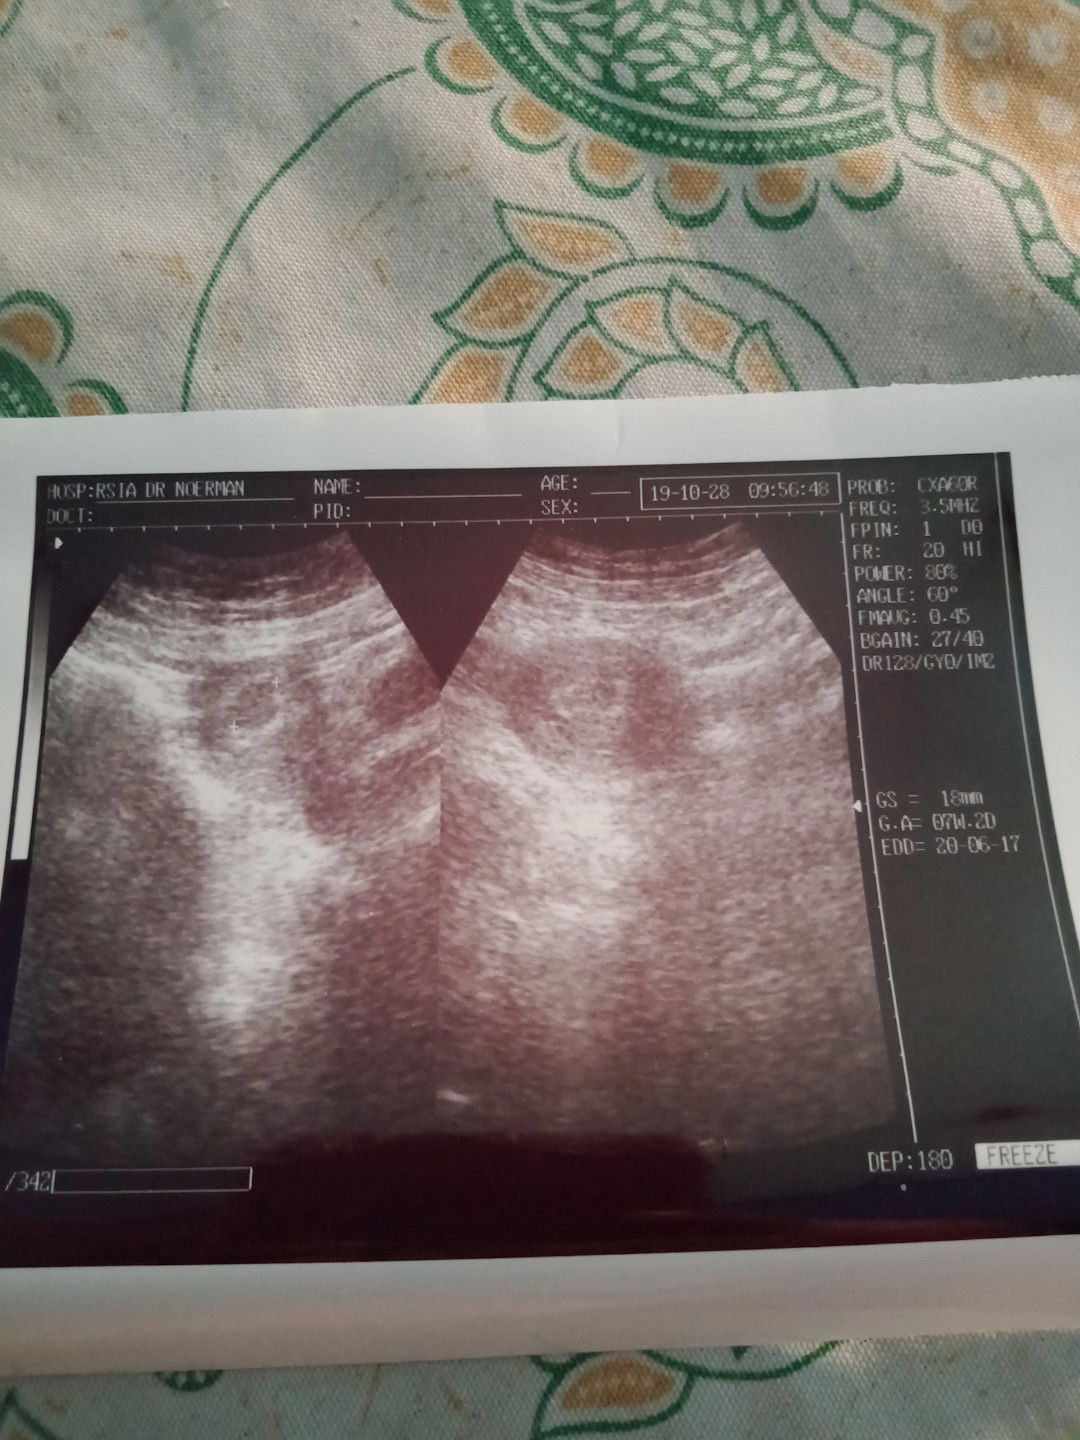

apa kah ini yag di sbut lemah kandungn

Apa sih penyebab dari lemah kandungan